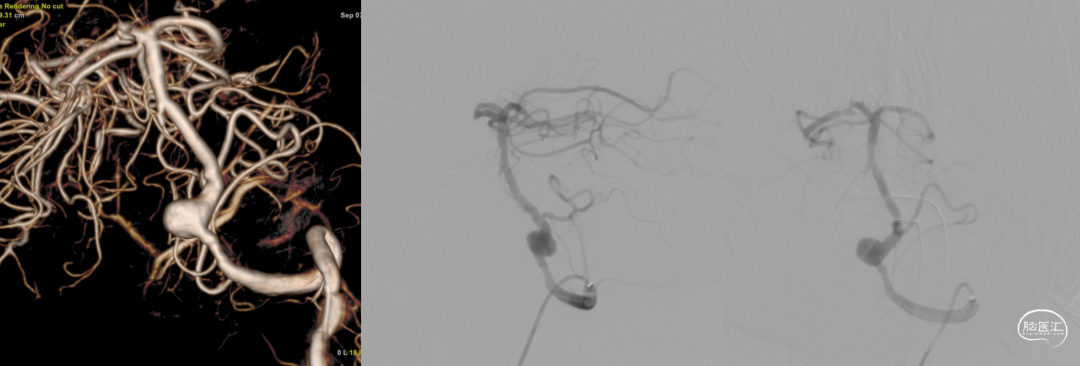

术前造影:

右颈

左椎

疏松填塞弹簧圈后正侧位造影。